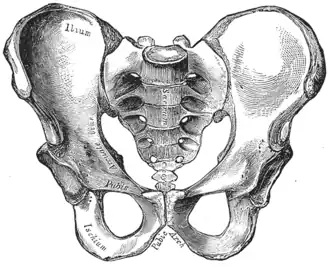

-

Becken -

Zugleich wird unter dem Begriff „Becken“ auch der knöcherne Teil dieses Körperabschnitts verstanden. Das knöcherne Becken besteht aus den beiden Hüftbeinen (Ossa coxae) und dem Kreuzbein (Os sacrum), sie bilden den Beckengürtel oder auch Beckenring (Cingulum membri pelvini). Bei Säugetieren (einschließlich des Menschen) ist das knöcherne Becken mit der Wirbelsäule über das Iliosakralgelenk gelenkig, aber wenig beweglich[1], verbunden. Durch seine Festigkeit und Stabilität gibt der Beckengürtel dem menschlichen Körper einen sicheren Stand und eine aufrechte Haltung. Zudem umgibt es die Beckenhöhle. Bei Tieren sorgt es dafür, dass die Hintergliedmaßen stabil am Rumpf verankert werden und der von ihnen produzierte Vorschub effektiv auf den Körper übertragen wird. Bei Krokodilen unterstützt der Beckengürtel die Lungenventilation.[2]

Beide Hüftbeine sind über das Kreuzbein-Darmbein-Gelenk (Articulatio sacroiliaca) mit dem Kreuzbein verbunden. Dieses Gelenk ist eine Amphiarthrose, also ein straffes Gelenk, das kaum Bewegungen ausführen kann, aber für die Federung der Wirbelsäule von großer Wichtigkeit ist. An der Vorderseite haben die beiden Hüftbeine eine knorpelige Verbindung über die Schambeinfuge (Symphysis pubica). Bei Tieren liegt die Verbindung zwischen beiden Hüftknochen an der Unterseite und schließt Scham- und Sitzbein ein (Symphysis pelvica).

Geschlechtsunterschiede am knöchernen Becken und Variationen

Das weibliche und männliche Becken beim Menschen unterscheiden sich deutlich. Während bei der Frau die beiden Beckenschaufeln ausladender sind und das Hüftbeinloch (Foramen obturatum) eine eher dreieckige Form hat, ist das männliche Becken hoch, schmal und eng. Auch der Beckenausgang ist beim weiblichen Becken breiter; der Winkel zwischen beiden Schambeinästen ist beim weiblichen Becken größer als 90° (Arcus pubicus), während er beim männlichen Becken nur etwa 70° (Angulus subpubicus) beträgt. In der Anatomie und der Geburtshilfe werden zur Beschreibung der Beckenform standardisierte Conjugata (Ansicht von lateral) und Diameter (Ansicht von kranial oder kaudal) verwendet.